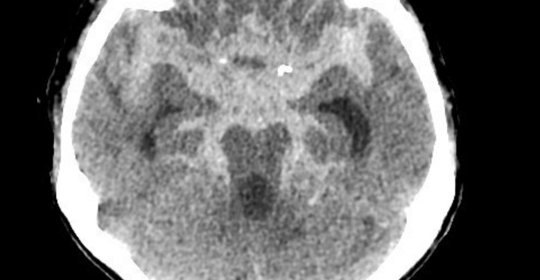

腦幹出血:顱內壓控制、生命支援、抗高血壓

腦幹出血:原因、症狀與治療

腦幹出血:原因與恢復

腦幹出血:清醒機率與前兆

腦幹出血:症狀、嚴重性與後遺症